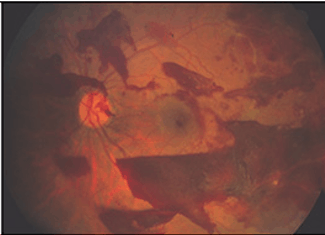

2. PDR (Proliferative Diabetic Retinopathy)

PDR is the more advanced stage of diabetic retinopathy.

- The retina starts growing new blood vessels: a process called neovascularisation

- These fragile new vessels often bleed within the eye called: vitreous haemorrhage

- If they only bleed a little, you might see a few floaters.

- If they bleed a lot, vision may be blocked.

- These new blood vessels can form fibrous scar tissue.

- Scar tissue can pull on the retina and cause detachment of the retina called: tractional retinal detachment.

Tractional Retinal Detachment

Abnormal blood vessels

Abnormal bleeding in eye